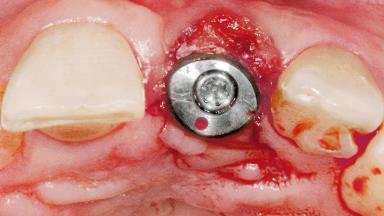

Late Flapless Placement of an Implant in a Maxillary Left Central Incisor Site

Type of Implants One-Piece

Attachment One-Piece

Placement Protocol Early or late implant placement